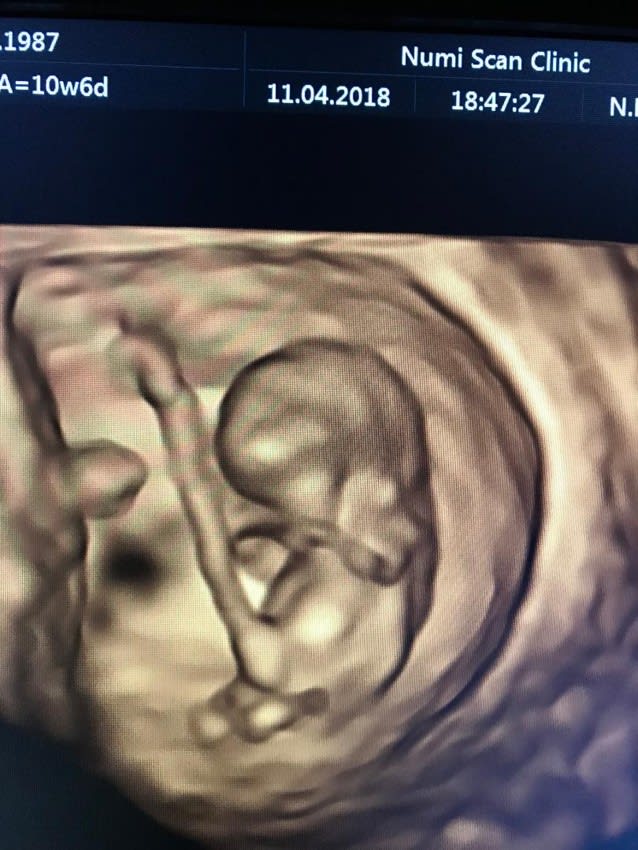

This baby scan package is for early pregnancy - usually between 7-15 weeks - and is designed for parents who would like reassurance and to see a heartbeat. Also, if you are unsure of your dates or cannot get to see your midwife as soon as you would like, our early pregnancy baby scans are perfect for giving you an estimated due date and confirm if a single or multiple pregnancy. Please note we use a transabdominal (across your tummy) probe for this scan. It is important to drink 1 litre of water 45 minutes before the scan.

2D Dating baby scan

FREE 4D Peek

This baby scan is for early pregnancy usually between 7-15 weeks. This package is designed for parents who would like continued reassurance throughout the first trimester and to see a heartbeat on each ultrasound scan. This is a great way to watch baby grow with your partner and see your baby in 4D throughout the first trimester. Please note we use a transabdominal (across your tummy) probe for this scan. It is important to drink 1 litre of water 45 minutes before the scan.